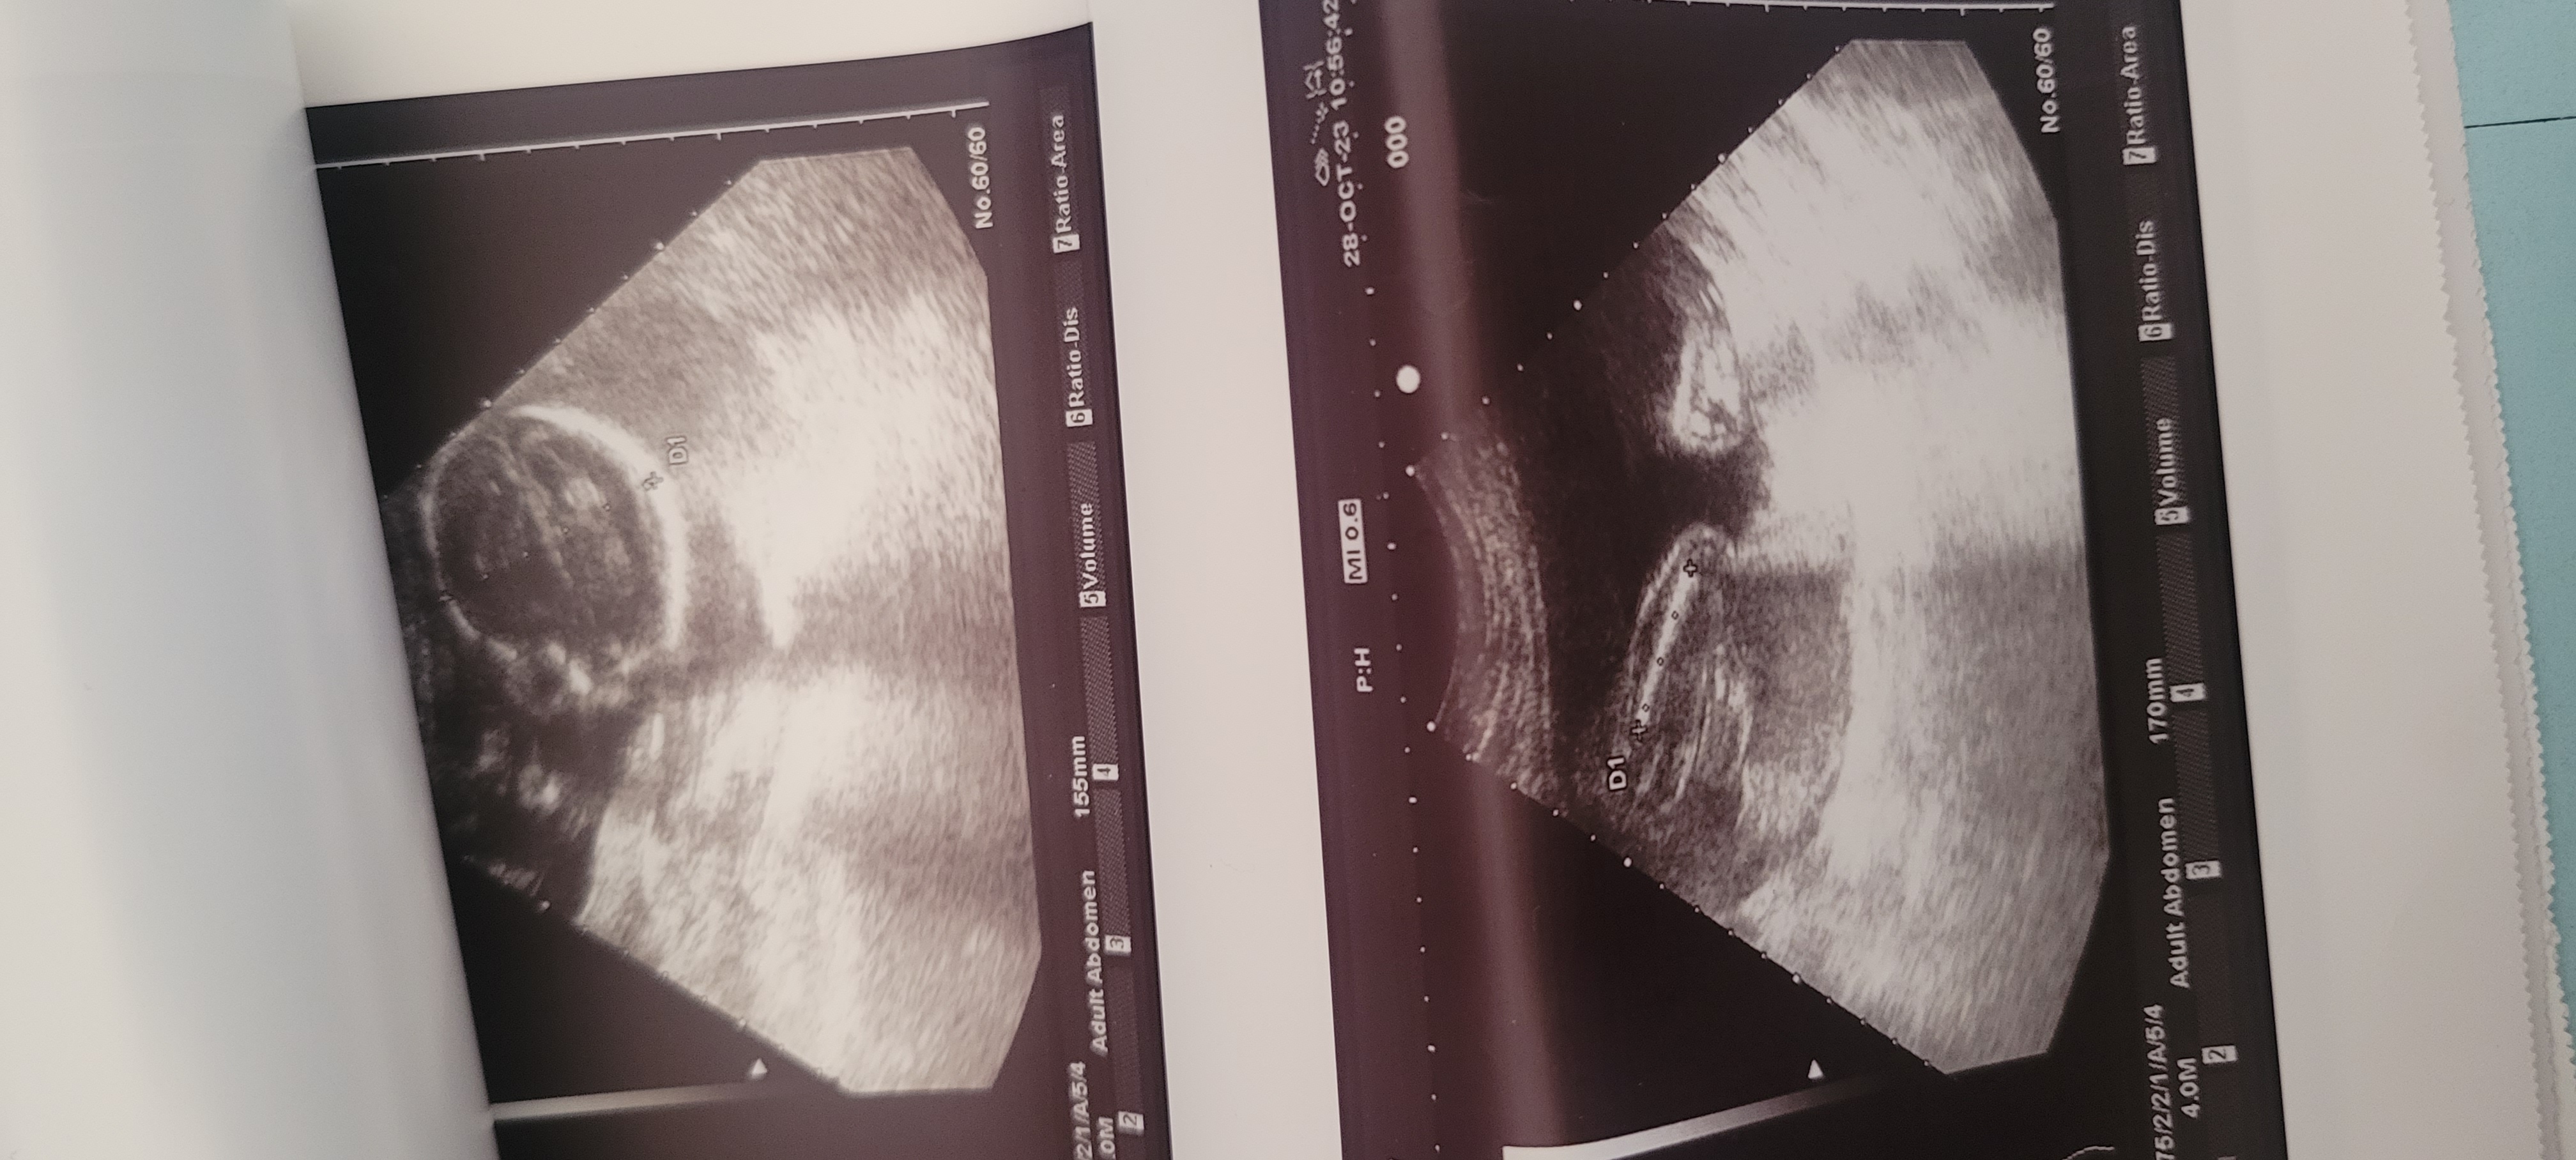

معرفه نوع الجنين بنت او ولد